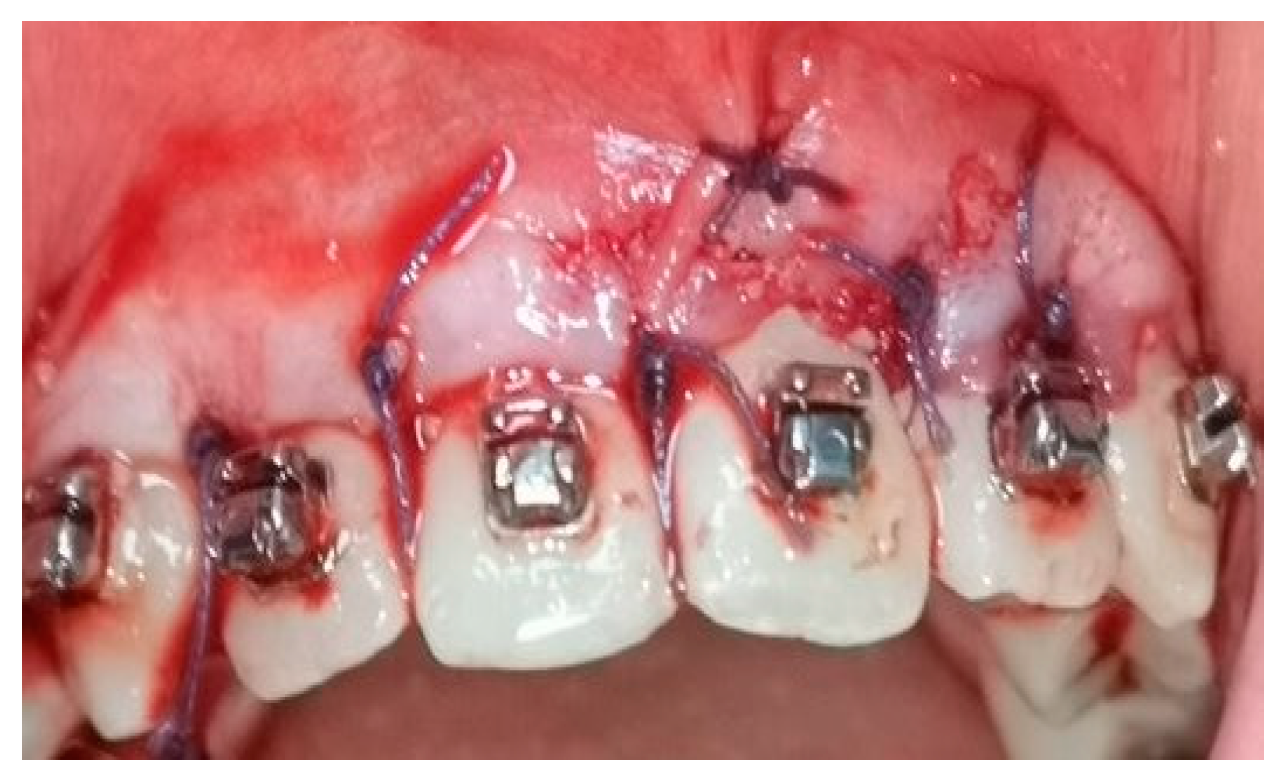

2.5. Surgical Phase

2.6. Collection of the Radiological Data